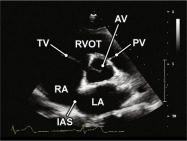

| 2.8. Mặt cắt trục ngắn cạnh ức (ngang mức các đại động mạch) khu trú vào van động mạch chủ |

||||||||

|

|

Cửa sổ siêu âm cạnh ức

Mặt cắt trục ngắn cạnh ức Xoay đầu dò 90O từ mặt cắt trục dài cạnh ức và ngửa đầu dò để ghi hình rõ các cấu trúc giải phẫu ngang mức động mạch chủ |

Van động mạch chủ (AV)

Nhĩ trái (LA) Nhĩ phải (RA) Van ba lá (TV) Đường ra thất phải (RVOT) Van động mạch phổi (PV) Vách liên nhĩ (IAS) |

|||||